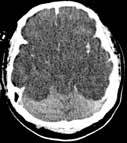

Perfusion CT in a patient with stroke demonstrates the part of the brain with severely decreased blood flow (arrows).